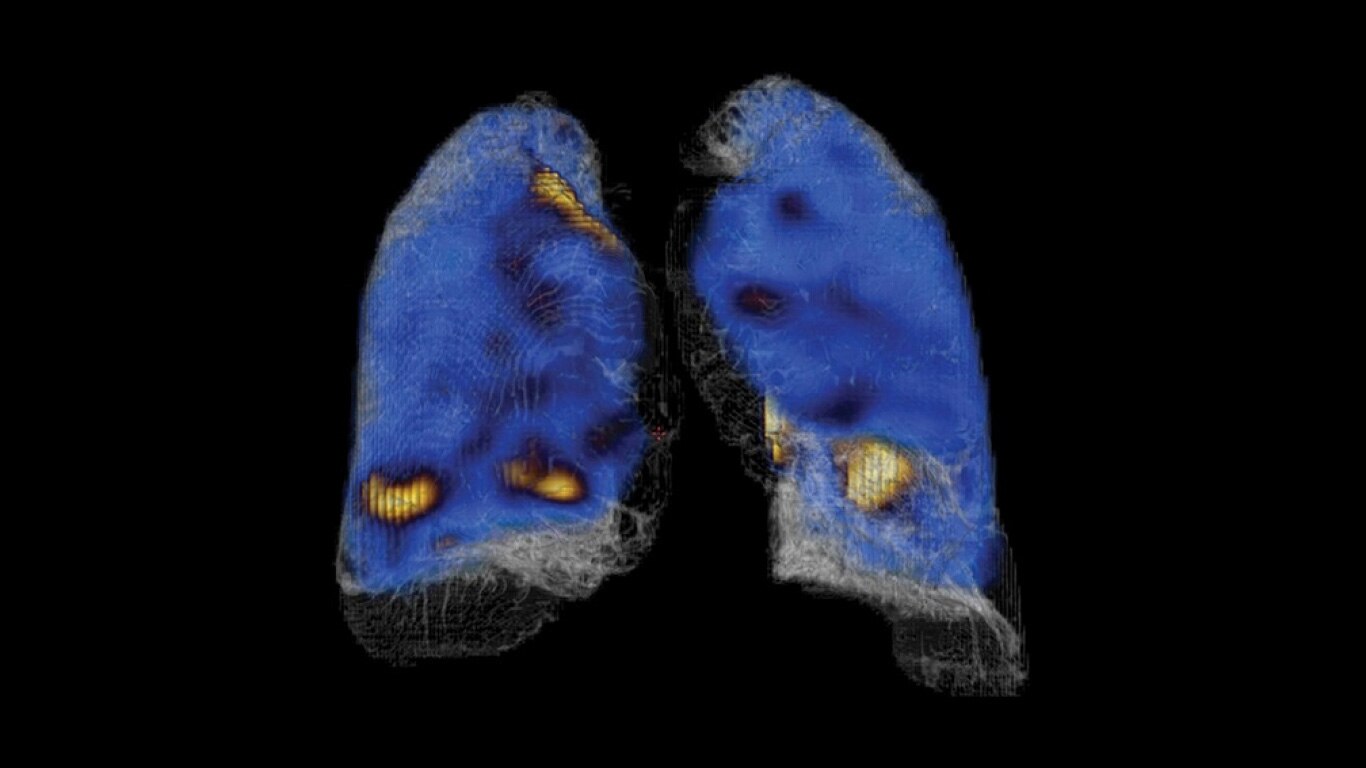

Experience a new productivity hub for hybrid imaging. By automating SPECT/CT reconstruction, SmartConsole simplifies the workflow for complex hybrid and quantitative protocols and allows technologists to review results directly at the scanner console. It also allows physicians to review scans remotely from mobile devices. They can modify processing settings and initiate study processing anytime, anywhere across a LAN or a WAN*.

SmartConsole enables a noticeable improvement in productivity. Now, a physician can provide their input remotely and digitally. For example, physicians can review a whole-body bone scan directly on their tablet or other mobile device and define the scan range limits they need from wherever they are. The time saved with this switch to a digital workflow helps make it possible to complete exams in predictable time slots.